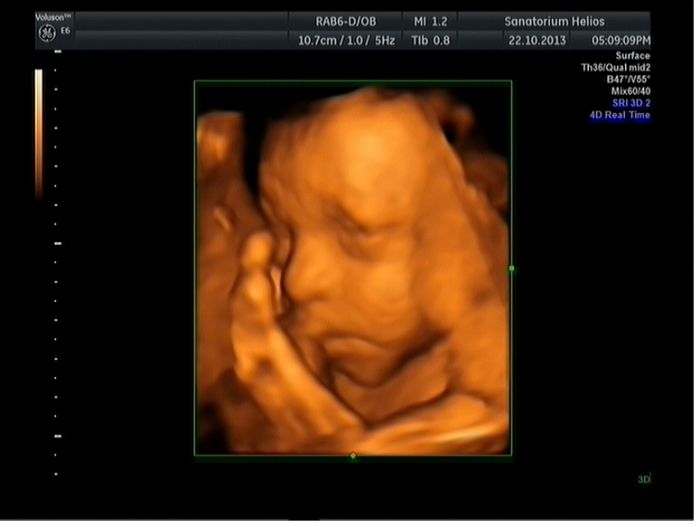

[379828] Ahoj Včelko, chtěla jsme se zeptat na to 3D jak jsi byla

to jsi se sama jen tak někam objednala nebo to ti udělal tvůj Dr.? Já totiž bych taky chtěla mooc to 3D...sice jak sem byla na II.screeningu ve 20 týdnu, tak mi ho dělali, ale malá byla celou dobu zádičkama a tak jsme nic neviděli a taky bych chtěla alespon ještě jednou mít potvrzené pohlaví

jelikož nám ve 12 týdnu řekli, že to asi bude kluk...pak ve 20 tt, že to bude holčička, tak bych to chtěla mít alespon ještě jednou potvrzené. Jelikož můj gynekolog pohlaví neříká...nevím, jestli to nevidí nebo nedokáže poznat, ale jsem si jistá, že ted v tom 30 tt na UZ se nic od něj nedozvím